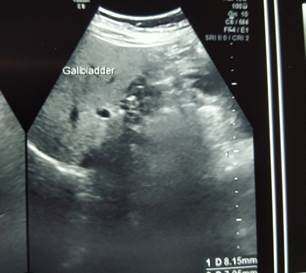

The ultrasound of the abdomen showed that the liver had increased reflectivity. The biliary channels were normal. The gall bladder was contracted and had few echogenic foci in the lumen, the largest of which was 9.3mm. The wall thickness was 3.6mm. CBD was dilated (7.9mm) and showed echogenic foci of 8.1mm in the lumen. It gave the impression of cholelithiasis with choledocholithiasis and associated Grade I Fatty Liver (Figure 1).

Figure 1: USG showing gallstones and dilated CBD stones